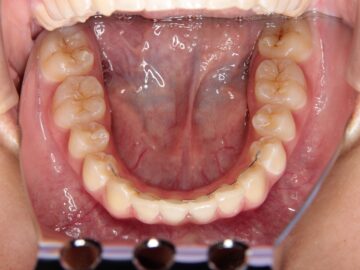

治療後

第一期治療で大臼歯の咬み合わせを整え、第二期治療で上下顎の歯にブラケットをつけて非抜歯治療を目指す。